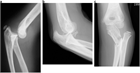

1. 肘関節脱臼・骨折などに伴う急性靱帯損傷で肘関節不安定性がある場合には、一次的靭帯修復を行うことが推奨される。